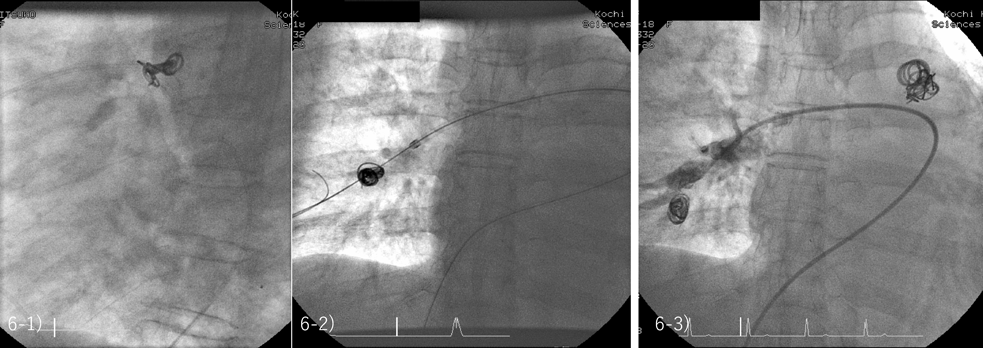

複数のコイルが絡まって肺動脈末梢に脱落・遊走した場合,太いデリバリーシースを肺動脈内に進め,肺動脈内でコイルの回収を目指す.しかし,コイルがデリバリーシース内に入ってこない場合,当然被ばく量は多くなり,万一,コイルが三尖弁に引っかかれば開胸手術が必要になる.苦肉の策ではあるが,私の経験を述べてみたい(Fig. 6).他院に出張でPDAの2症例を閉じに行った際の脱落例(67歳女性)である.F-coilを3個留置した後に振り返るとコイルは塊状になり右肺動脈内に脱落していた.さらに1例のPDAを閉鎖しなければならなかったこと,物品も限られ脱落したコイルの回収にてこずる可能性,確率は低いもののデリバリーシース内に収納できず三尖弁に引っかかれば,開胸手術が必要になる可能性などを考える必要があった.迷った末,精神的ストレスを軽減するためにも,幸いにも用意してあった0.052’ Gianturco coil[Cook社;Turlock, CA]1個とF-coil 3個,0.035’ platinum pushable coil[Boston Scientific社;Marlborough, MA]1個の計5個を用いて,まずPDAを閉鎖した.その上で遊走したコイルを一塊としてより末梢の肺動脈内に押し込んで手技を終了した.もちろんカテーテル検査前にはコイルが脱落する可能性,回収が困難な場合にはそのまま放置する場合もありうるが,生活にはほとんど影響がないことを説明していた.ベストとは言えないが,90点を目指して30点になってしまうこともある.実質影響の少ない70点で抑えるか90点を目指すのか,周囲の状況,自分の力量,患者の年齢や生活状況などを,術者は常に天秤にかけて決定する必要がある.

Fig. 6 Push the migrated coils more peripherally to decrease the adverse effects of occluding the normal peripheral pulmonary artery

6-1) Three Flipper® PDA coils were deployed in the PDA of 67 years old woman. 6-2) However, they migrated into the right pulmonary artery. 6-3) As we didn’t have enough time and the delivery sheath suitable for retrieving 3 coils together, we pushed them more distantly after we occluded the PDA successfully with 5 coils including 0.052’ Gianturco® coil with 8 mm in diameter. The patient condition got much better after the procedure. PDA, patent ductus arteriosus